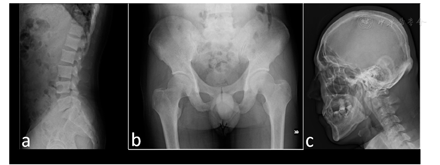

辅助检查:血常规:白细胞4.18×109/L,血红蛋白94 g/L,血小板189×109/L,网织红细胞2.45%;尿便常规正常;肝肾功能:丙氨酸转氨酶11 U/L,门冬氨酸氨基转移酶22 U/L,γ-谷氨酰胺转肽酶24 U/L,乳酸脱氢酶199 U/L(0~250),肌酐55 μmol/L,血钾4.2 mmol/L,血钠140 mmol/L;血沉38 mm/h,超敏C反应蛋白0.62 mg/L。骨代谢相关指标:血钙2.10 mmol/L(2.13~2.70),血磷0.88 mmol/L(0.81~1.45),ALP 1 366 U/L(45~125),血镁0.88 mmol/L(0.70~1.10),肌酸激酶49 U/L(24~195);24 h尿钙0.32 mmol,24 h尿磷16.38 mmol;PTH 144.0 pg/ml(12.0~65.0);β-CTX 4.61 ng/ml(0.26~0.51),25-(OH)维生素D3 12.7 ng/ml;骨密度(Z值):L1-L4为2.4,全髋为-0.6;X线片:部分胸腰椎椎体、骨盆骨质密度不均(图1);骨扫描:全身骨骼多发代谢摄取异常增强,呈"超级骨显像"(图2a)。

注:a:腰椎骨密度明显增加;b:骨盆骨质密度不均匀;c:头颅板障欠规则,骨质密度尚均匀